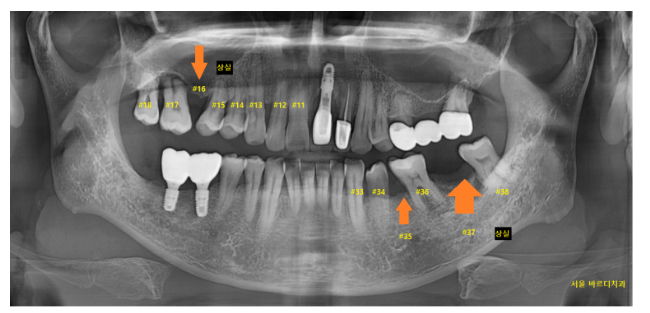

고덕역 근처 치과 방문해 주신 환자분입니다.

x-ray 사진에서 군데 군데 비워져 있는 곳이

눈에 보입니다.

오른쪽 윗니 어금니 1개

왼쪽 아래 어금니 2개

총 3개가 없는 상태입니다.